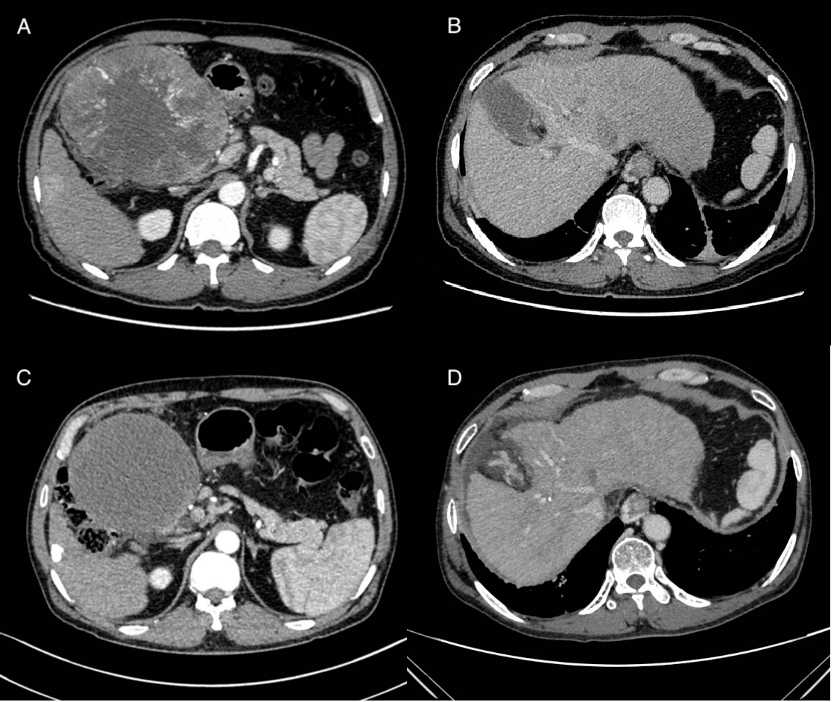

经过一系列详细检查,发现洪先生的病情较为复杂,恐怕很难彻底根治。增强CT结果提示“肝左叶可见巨大外生性肿物,范围约11.5×10.8×14.2cm”,同时还发现“肝内存在多发转移”,伴有“肝左静脉内及肝左静脉入下腔静脉处可见低密度灶,考虑瘤栓”。这么大的一个肿瘤,而且有了肝内转移,这意味着洪先生得到根治的可能性非常低。另一方面,洪先生还合并有严重的乙肝肝硬化,这既是发生肝癌的罪魁祸首,同时也增加了肿瘤复发转移的风险、降低了各种治疗抗肿瘤治疗的耐受性和治疗效果。

A:2024-1-18基线:肝左叶巨大占位;B:2024-1-18基线:肝硬化、肝左静脉瘤栓、食管胃底静脉曲张;C:2024-5-27:钇90治疗后1月;D:2024-8-28术前:瘤栓较前缩小